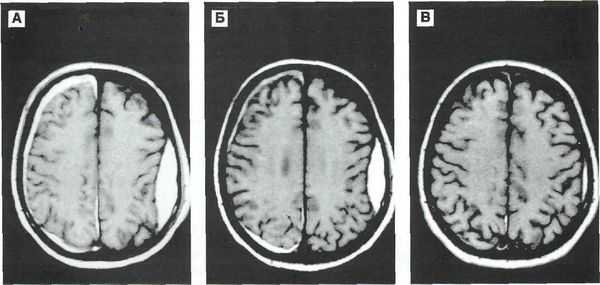

Основным методом диагностики УГМ в современных условиях является КТ головного мозга. Томографическая картина отличается в зависимости от тяжести ушиба. При легкой степени очаги с уменьшенной плотностью выявляются лишь в 40-50% случаев. В зоне ушиба на томограммах отмечается отечность, петехиальные кровоизлияния. Отечность может распространяться на всю долю мозга или даже на целое полушарие, приводить к умеренному сужению ликворных пространств.

Аксиальная КТ головного мозга без контрастного усиления. Определяется контузионный очаг в правой лобной доле, представленный геморрагическим компонентом, зоной детрита и отека

Ушиб средней тяжести характеризуется наличием на томограммах очагов ушиба в виде зон пониженной плотности. При геморрагическом пропитывании очаг ушиба может иметь повышенную плотность. При тяжелом ушибе томография визуализирует очаги как повышенной, так и пониженной плотности. В первом случае речь идет о сгустках крови, во втором — об участках размозжения и отека. При крайне тяжелых поражениях зона деструкции церебральной ткани уходит вглубь к подкорковым структурам.

В ходе лечения КТ также проводят в динамике. Наблюдения показывают, что в случае легкой или средней тяжести ушиба с течением времени происходит полное исчезновение очаговых изменений. В случае тяжелого УГМ наблюдается уменьшение площади очагов деструкции, а затем их трансформация в кисты головного мозга или участки атрофии. Чем тяжелее ЧМТ, тем более медленно проходят указанные изменения, визуализируемые при помощи КТ.